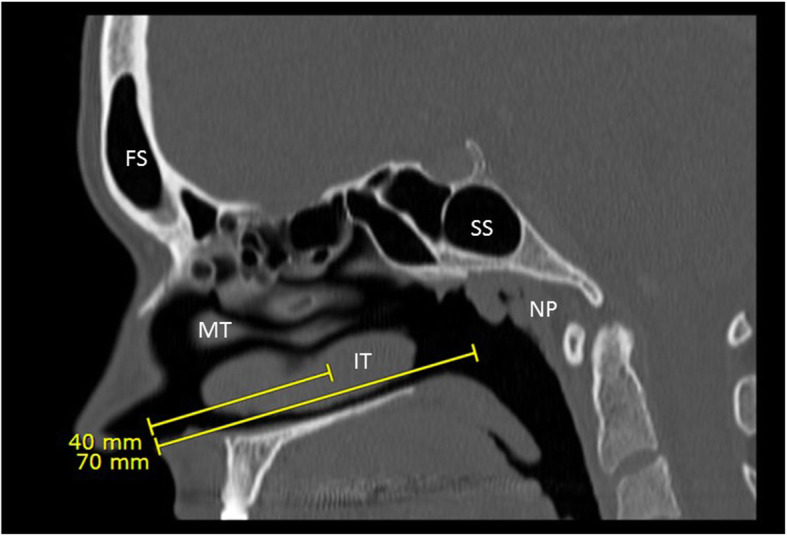

This review has demonstrated significant heterogeneity in nasopharyngeal swab performance instructions across Canada. The bottom line is that a swab needs to be inserted to the appropriate depth in order to reach the nasopharynx if one is to perform a nasopharyngeal swab (Fig. 1, Supplemental video 1). As experts in regional anatomy of the head and neck, otolaryngologists can provide a great service by actively engaging with their local and regional health authorities to train proper technique and anatomical knowledge.

Fig. 1.

Sagittal CT view of nose and nasopharynx (50-year-old Caucasian female). Areas reached by recommended measured depth of insertion are demonstrated. FS - Frontal Sinus, MT - Middle Turbinate, IT - Inferior Turbinate, SS - Sphenoid Sinus, NP - Nasopharynx

Minimal data has been published regarding the depth of the nasopharynx. A study by Lim and Lee [32] from Korea demonstrated in a series of 200 individuals that the average distance from nostril to nasopharynx surface was 9.4 ± 0.6 cm in females and 10.0 ± 0.5 cm in males. They also found that the average distance from philtrum to tragus (akin to measuring nostril to ear distance) in the same set of patients was 14.4 ± 0.5 cm in females and 15.1 ± 0.6 cm in males. A study examining 227 subjects demonstrated that the distance from nostril to face of sphenoid was 68 ± 4 mm in females and 71 ± 6 mm in males [33], which falls short of the nasopharynx. As such, in order to reach the nasopharyngeal mucosa, a swab should be inserted to a depth of two-thirds to the full distance from nostril to ear, or at least nine centimeters, and stopped when resistance is met.